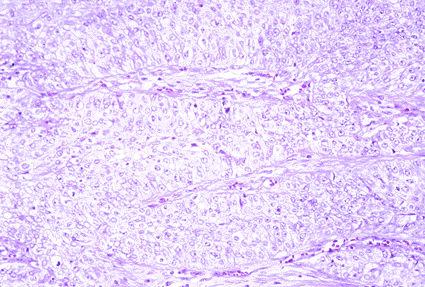

Several cases of HNPCC (hereditary nonpolyposis colorectal cancer).

[ Image ID:71 ]

Criteria of Hist.Classification

Malignant epithelial tumor/Others

Other/

Histology